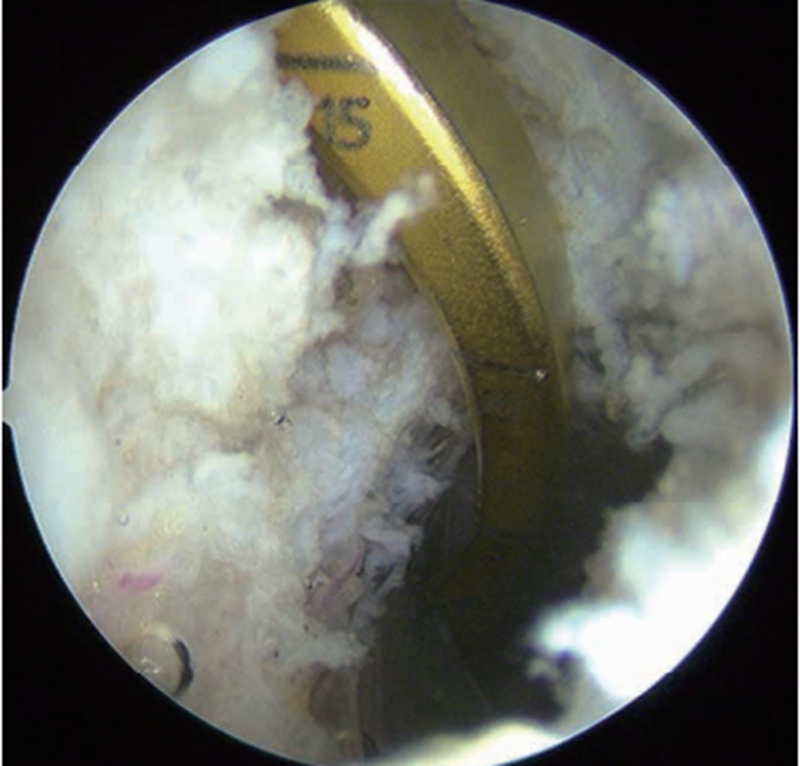

3.制备胫骨隧道

做膝关节后内与后外侧入路(图5),适当清理PCL残端周围滑膜、脂肪和后纵隔,显露PCL胫骨止点及其下方至少20mm深度的胫骨后缘(图6)。胫骨定位器从髌内侧入路置入,跨过ACL上方从PCL残端内侧绕至胫骨后方斜坡下定位。为避免“杀手转角”(killer turn)(图7),胫骨定位器前端应尽量伸至胫骨平台下方20mm或更低处(图8),跨过PCL在原斜坡上的止点,以确保移植物出胫骨隧道内口后附着处为隧道钝角,减少韧带磨损切割(图9)。

图5 膝关节后内侧入路建立方法

从膝关节后外侧入路经后外侧间室,穿过后纵隔到后内侧间室,光源照射直视下做后内侧入路

图6 PCL胫骨残端后方情况

适当清理PCL残端周围滑膜、脂肪和后纵隔,显露PCL胫骨止点及其下方至少20mm深度

图7 PCL胫骨“杀手转角”示意图

如在原PCL止点斜坡解剖重建PCL胫骨止点,移植物在胫骨出口处压在锐角的骨隧道一侧,造成移植物切割损伤,称为杀手转角

图8 PCL胫骨止点定位

在平台以下20mm处定位PCL胫骨隧道内口

图9 PCL胫骨止点避免“杀手转角”

如在胫骨平台20mm以下制备胫骨隧道,移植物出胫骨隧道内口后附着处为隧道钝角,减少韧带磨损切割

胫骨隧道外口放置在胫骨嵴偏外侧(图10),能更好地减少PCL移植物转折角以及在胫骨隧道内口的接触应力,降低韧带磨损或过度负荷。以后内侧入路为观察通道,从后外侧入路插入关节镜通道鞘管以保护后方血管、神经。直视下打入导针后,用移植物同号直径空心钻制备胫骨隧道。预置牵引线,并将关节镜通道鞘管置入牵引线前方以备协助牵拉移植物经过隧道。牵引线穿过胫骨和股骨隧道,在后方关节镜鞘的辅助牵引下将移植物引至合适位置。先固定股骨侧,固定胫骨侧前应将膝关节置于0°~30°屈伸范围,向前托起胫骨,避免其后坠,用9.1kg(20lb)的力量拉紧移植物并将其固定于胫骨侧(图11)。